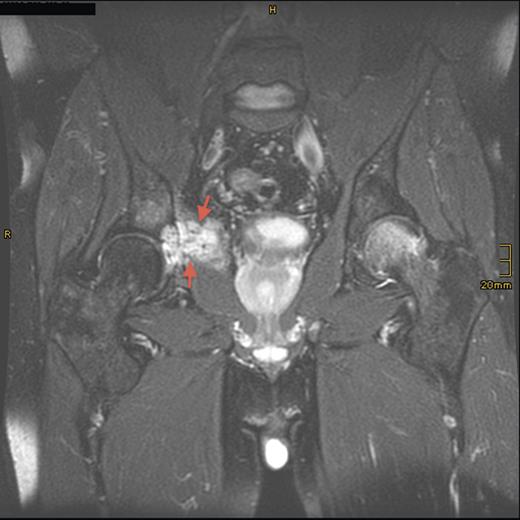

Eight years later, the patient presented with hip pain on the same side over a longer period. CT scan and MRI revealed tumor recurrence (Fig. 2) on the dorsomedial circumference of the acetabulum with a bone defect 2 cm in diameter. Signs of loosening of the cup of the hip arthroplasty were considered secondary. Biochemical evaluation revealed hypophosphatemia with 0.69 mmol/l of phosphate, normal serum calcium of 2.42 mmol/l and a secondary hyperparathyroidism with parathyroid hormone of 85.7 ng/l (normal range: 15–65 ng/l). An octreotide scan of the right hip showed massive enhancement of the acetabulum. Assessment of FGF-23 was inconclusive.

CT sagittal scan showing a suspected osteolytic lesion (arrows) in the right os ilium (8 years after primary resection).